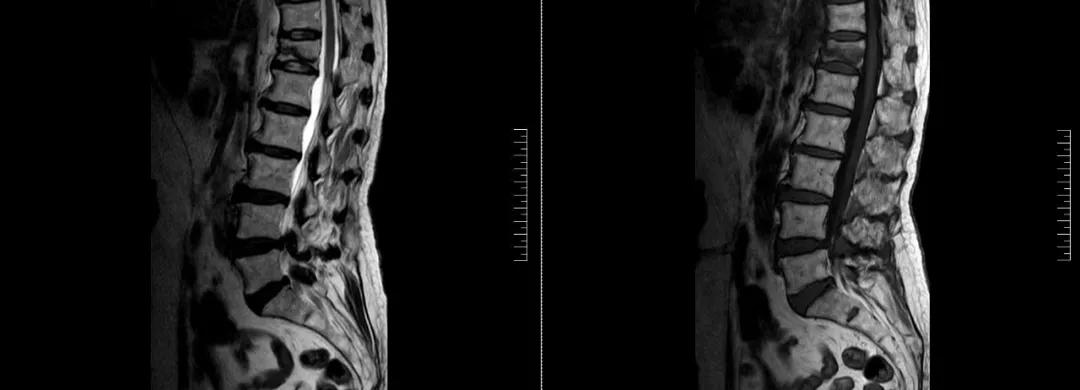

術前磁共振檢查提示腰1椎體新鮮壓縮性骨折

術后復查CT可見骨水泥彌散充分